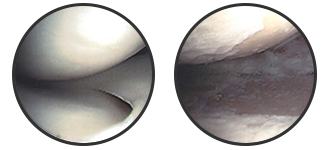

正常な膝軟骨変形性膝関節症の軟骨

膝の痛みの原因の多くは変形性膝関節症です。変形性膝関節症とは、膝関節の軟骨がすり減り、変形や関節炎を生じて、痛みが起こる病気です。正常な膝関節の軟骨は衝撃をやわらげたり関節の動きを滑らかにしますが、年をとったり無理に膝を使い続けることで軟骨がすり減ってしまいます。そしてほとんどの方が内側の軟骨がすり減ってしまい、O脚へと進行していきます。これが変形性膝関節症の原因といわれています。